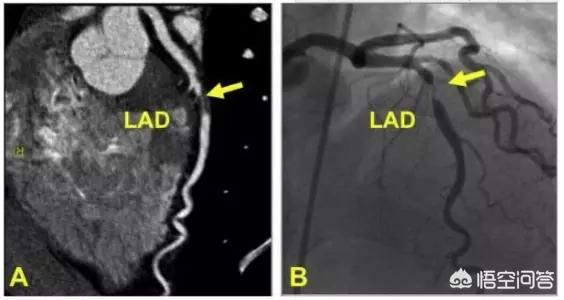

Examiner le projet :Coronarographie ou CTA

L'implantation de l'endoprothèse doit être réexaminée au niveau de la vascularisation après 9 à 12 mois. En fonction de vos symptômes et de la pathologie vasculaire à ce moment-là, votre médecin vous recommandera les examens appropriés.

En général, la coronarographie directe est recommandée pour les patients qui présentent encore des épisodes symptomatiques, qui ne sont pas complètement hémodialysés, qui subissent des interventions complexes, qui ont un diabète sucré comorbide et qui présentent une vasculopathie multibranche.